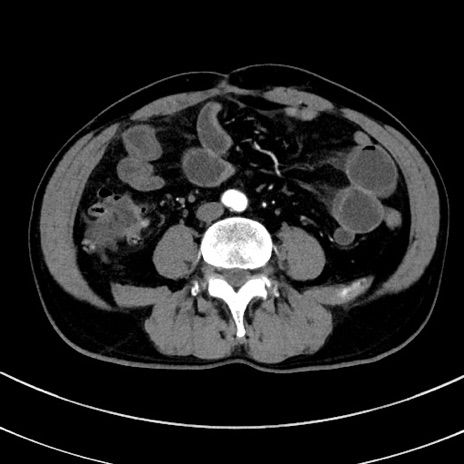

冠状断像

【症例】 60歳代男性

【主訴】 黒色吐物

【現病歴】 4日前から嘔気自覚、2日前の朝食後にも嘔気あり、自分で手で嘔吐反射起こし嘔吐したところ血が混ざっていたため受診。

【既往歴】 5年前汎発性腹膜炎を伴う急性虫垂炎で手術、高血圧、前立腺肥大症、高脂血症

【身体所見】 腹部正中に手術癩痕あり 腹部平坦・軟圧痛なし膨満感あり

【データ】WBC 8400、CRP 4.54